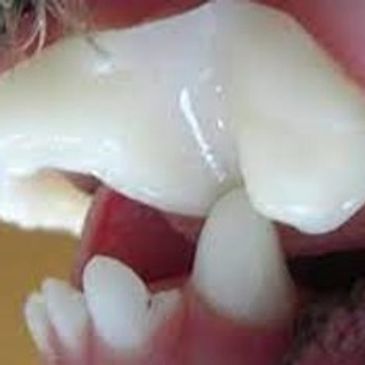

Conditions such as gingival hyperplasia can cause excessive gingival tissue development. This condition can be a genetic disorder or a result of administration of certain medications. Gingival hyperplasia causes deep periodontal pockets which can result in advanced periodontal disease and tooth loss. Excess gingiva should be removed to treat this condition and prevent periodontal disease.